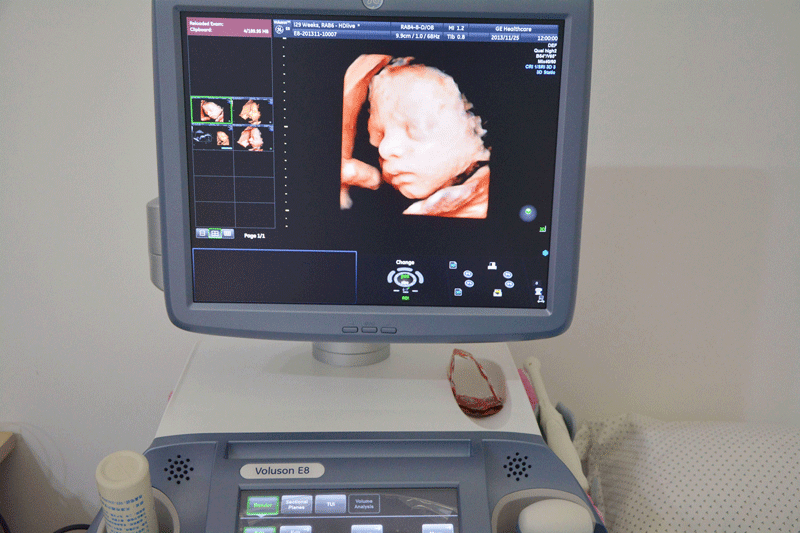

三维彩超,即彩色多普勒超声检查的一种,检查图像呈土黄色,通过多普勒超声仪器发出超声波,对体内各项器官进行成像。三维即其图像是立体的,可以更直观的看到器官的形态,及时发现病变并进行治疗。三维彩超常用于产检,用来判断胎儿的生长发育的情况或是否出现畸形等。

产检中,三维彩超通过测量子宫纵径、子宫体横径、子宫前后径这三条径线来观察胎儿是否正常。以及通过三维立体的成像,可以清晰的显示出胎儿各个内脏器官,以及面部器官、四肢的情况,来简单的判断胎儿是否存在畸形,包括胎儿是否患有先天性心脏病也是能够检查出来的。

24周的胎儿,其身体结构的生长发育已经很完善了,且胎儿大小也很合适,这时候做三维彩超可以很直观的看到胎儿的五官四肢、以及内脏器官,还能了解胎儿双顶径、头围、腹围、股骨长等发育情况。

2、清晰度不同

目前临床上维彩超检查是直接对胎宝宝先天头面部畸形的判断,可以拍到宝宝生长发育的局部立体图像。而四维相对于三维来说,会更清晰,对胎宝宝畸形,如唇腭裂、四肢发育畸形、脑膜膨出、脊柱裂、腹壁裂和心血管畸形等能够做早期诊断,并且能够立体显示胎宝宝的颜色、各器官的发育情况,甚至在母体内吸吮、睡觉等动态也可以捕捉到。。

三维和四维并不是彩色图片,只是和黑白色有差异,二者呈现的都是土黄色的画面。但三维的成像是静态的,是一张图片,而四维彩超则是动态的,像一张动图一样,并且有的医院会允许刻成光盘带回家收藏起来。